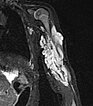

130x magnification (CD31 immunohistochemical staining to visualize vascular endothelial cells) shows intense brown staining of the endothelial structures. This proves the vascular character of the lesion. The vessels are typically arranged lobulated in infantile hemangioma as a vascular tumor.

At 130× magnification (WT1 staining), cytoplasmic positivity (brown staining of the endothelial cell layer) also argues against a vascular malformation and in favor of a vascular tumor, thus consistent with an infantile hemangioma.

In the 250× detail magnification of GLUT1 staining, infantile hemangioma capillaries exhibit characteristic immunohistochemical GLUT1 expression (brown staining of the endothelial cell layer), which normally shows positivity only in placental capillaries and vascular tumors derived from them. Hence, the assumption that infantile hemangiomas are derived from vascular precursor cells of the placenta. In other hemangiomas (e.g., congenital hemangiomas such as NICH or RICH), GLUT1 is negative. This is the most important differential diagnostic histological criterion for infantile hemangioma. The erythrocytes contained in the lumina also show GLUT1 positivity and thus serve as a positive internal control that the staining has worked well technically.